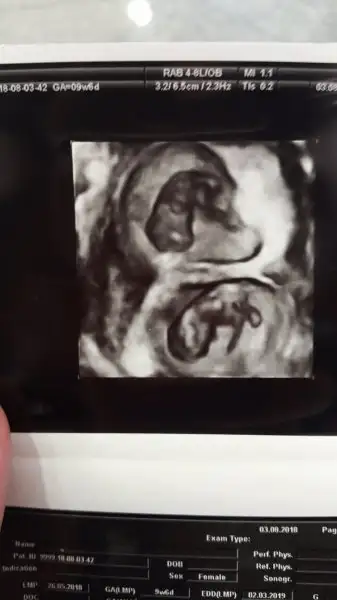

Kızlar Merhabaa..

Sabah doktora gitmiştik..

Önceki kontrolde hiçbişi anlamamıştım ama bu sefer her şeyi daha iyi idrak ettim ve aşırı mutlu oldum..

İki tane kıpır kıpır elleri kolları kımıl kımıl kuzu gördük.

O kadar güzellerdi ki.

Doya doya ekrana bakmaktan gözlerimi alamadım..

Bunlar benim kuzularım

İkisi de aynı gidiyor 9+4'ler :)